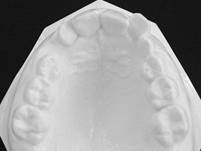

สภาพฟันหลังรักษา

ผู้ป่วยมีภาวะฟันสบเหลื่อมชนิด Class II Division II Overbite ได้รับการรักษาแบบหลายขั้นตอน ในขั้นแรกใช้เครื่องมือกระตุ้นแอกติเวเตอร์ KI II 2 และต่อมาใช้เครื่องกระตุ้นเพื่อจัดฟันแบบของ Prof. Sander (VDP) และเครื่องมือจัดฟันชนิดติดแน่น โดยใช้เครื่องมือจัดฟันชนิดถอดได้นาน 23 เดือน และเครื่องมือชนิดติดแน่น 17 เดือน